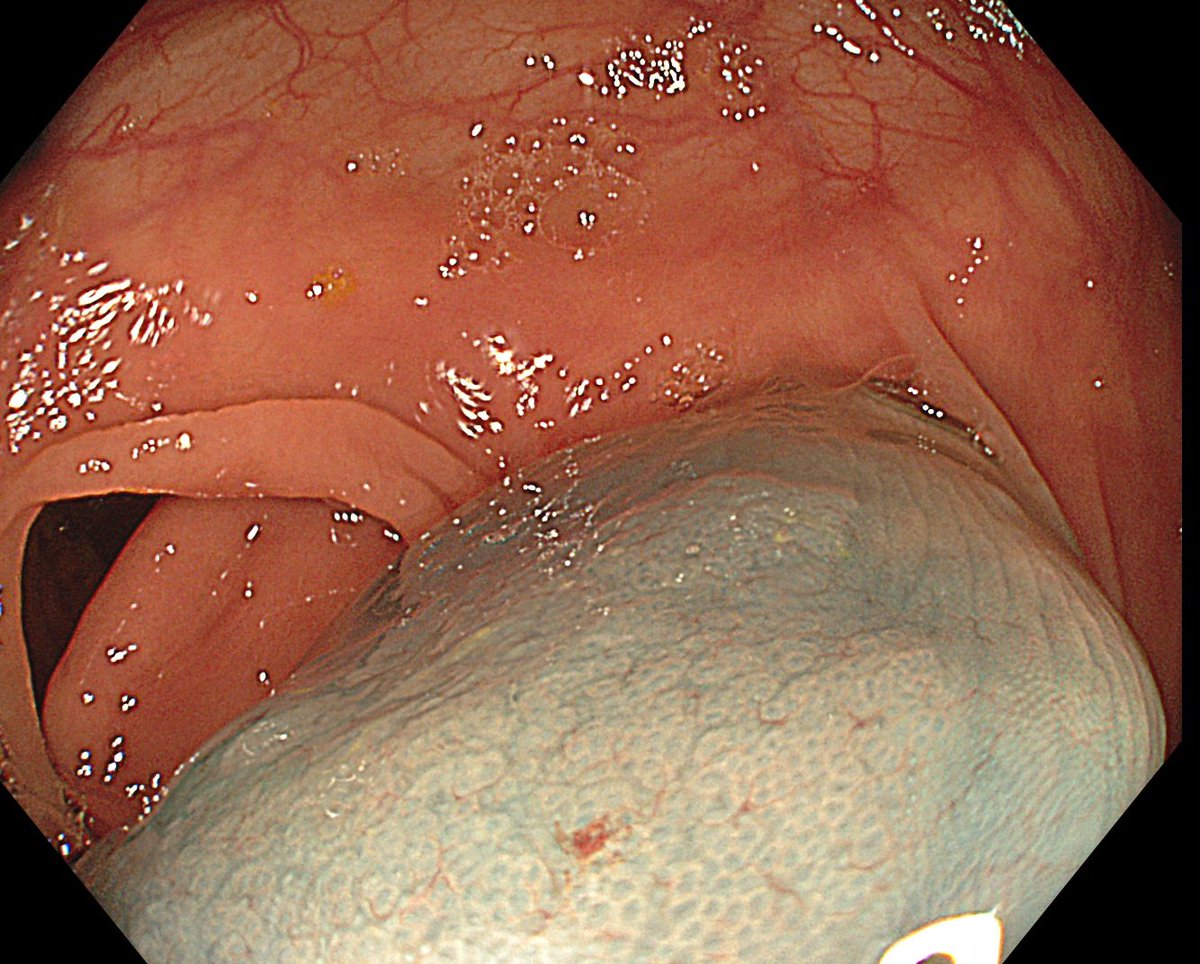

1. Antrum, low grade dysplasia. Removed via ESD. Specimen 43x32mm / dysplasia 20x13mm. R0